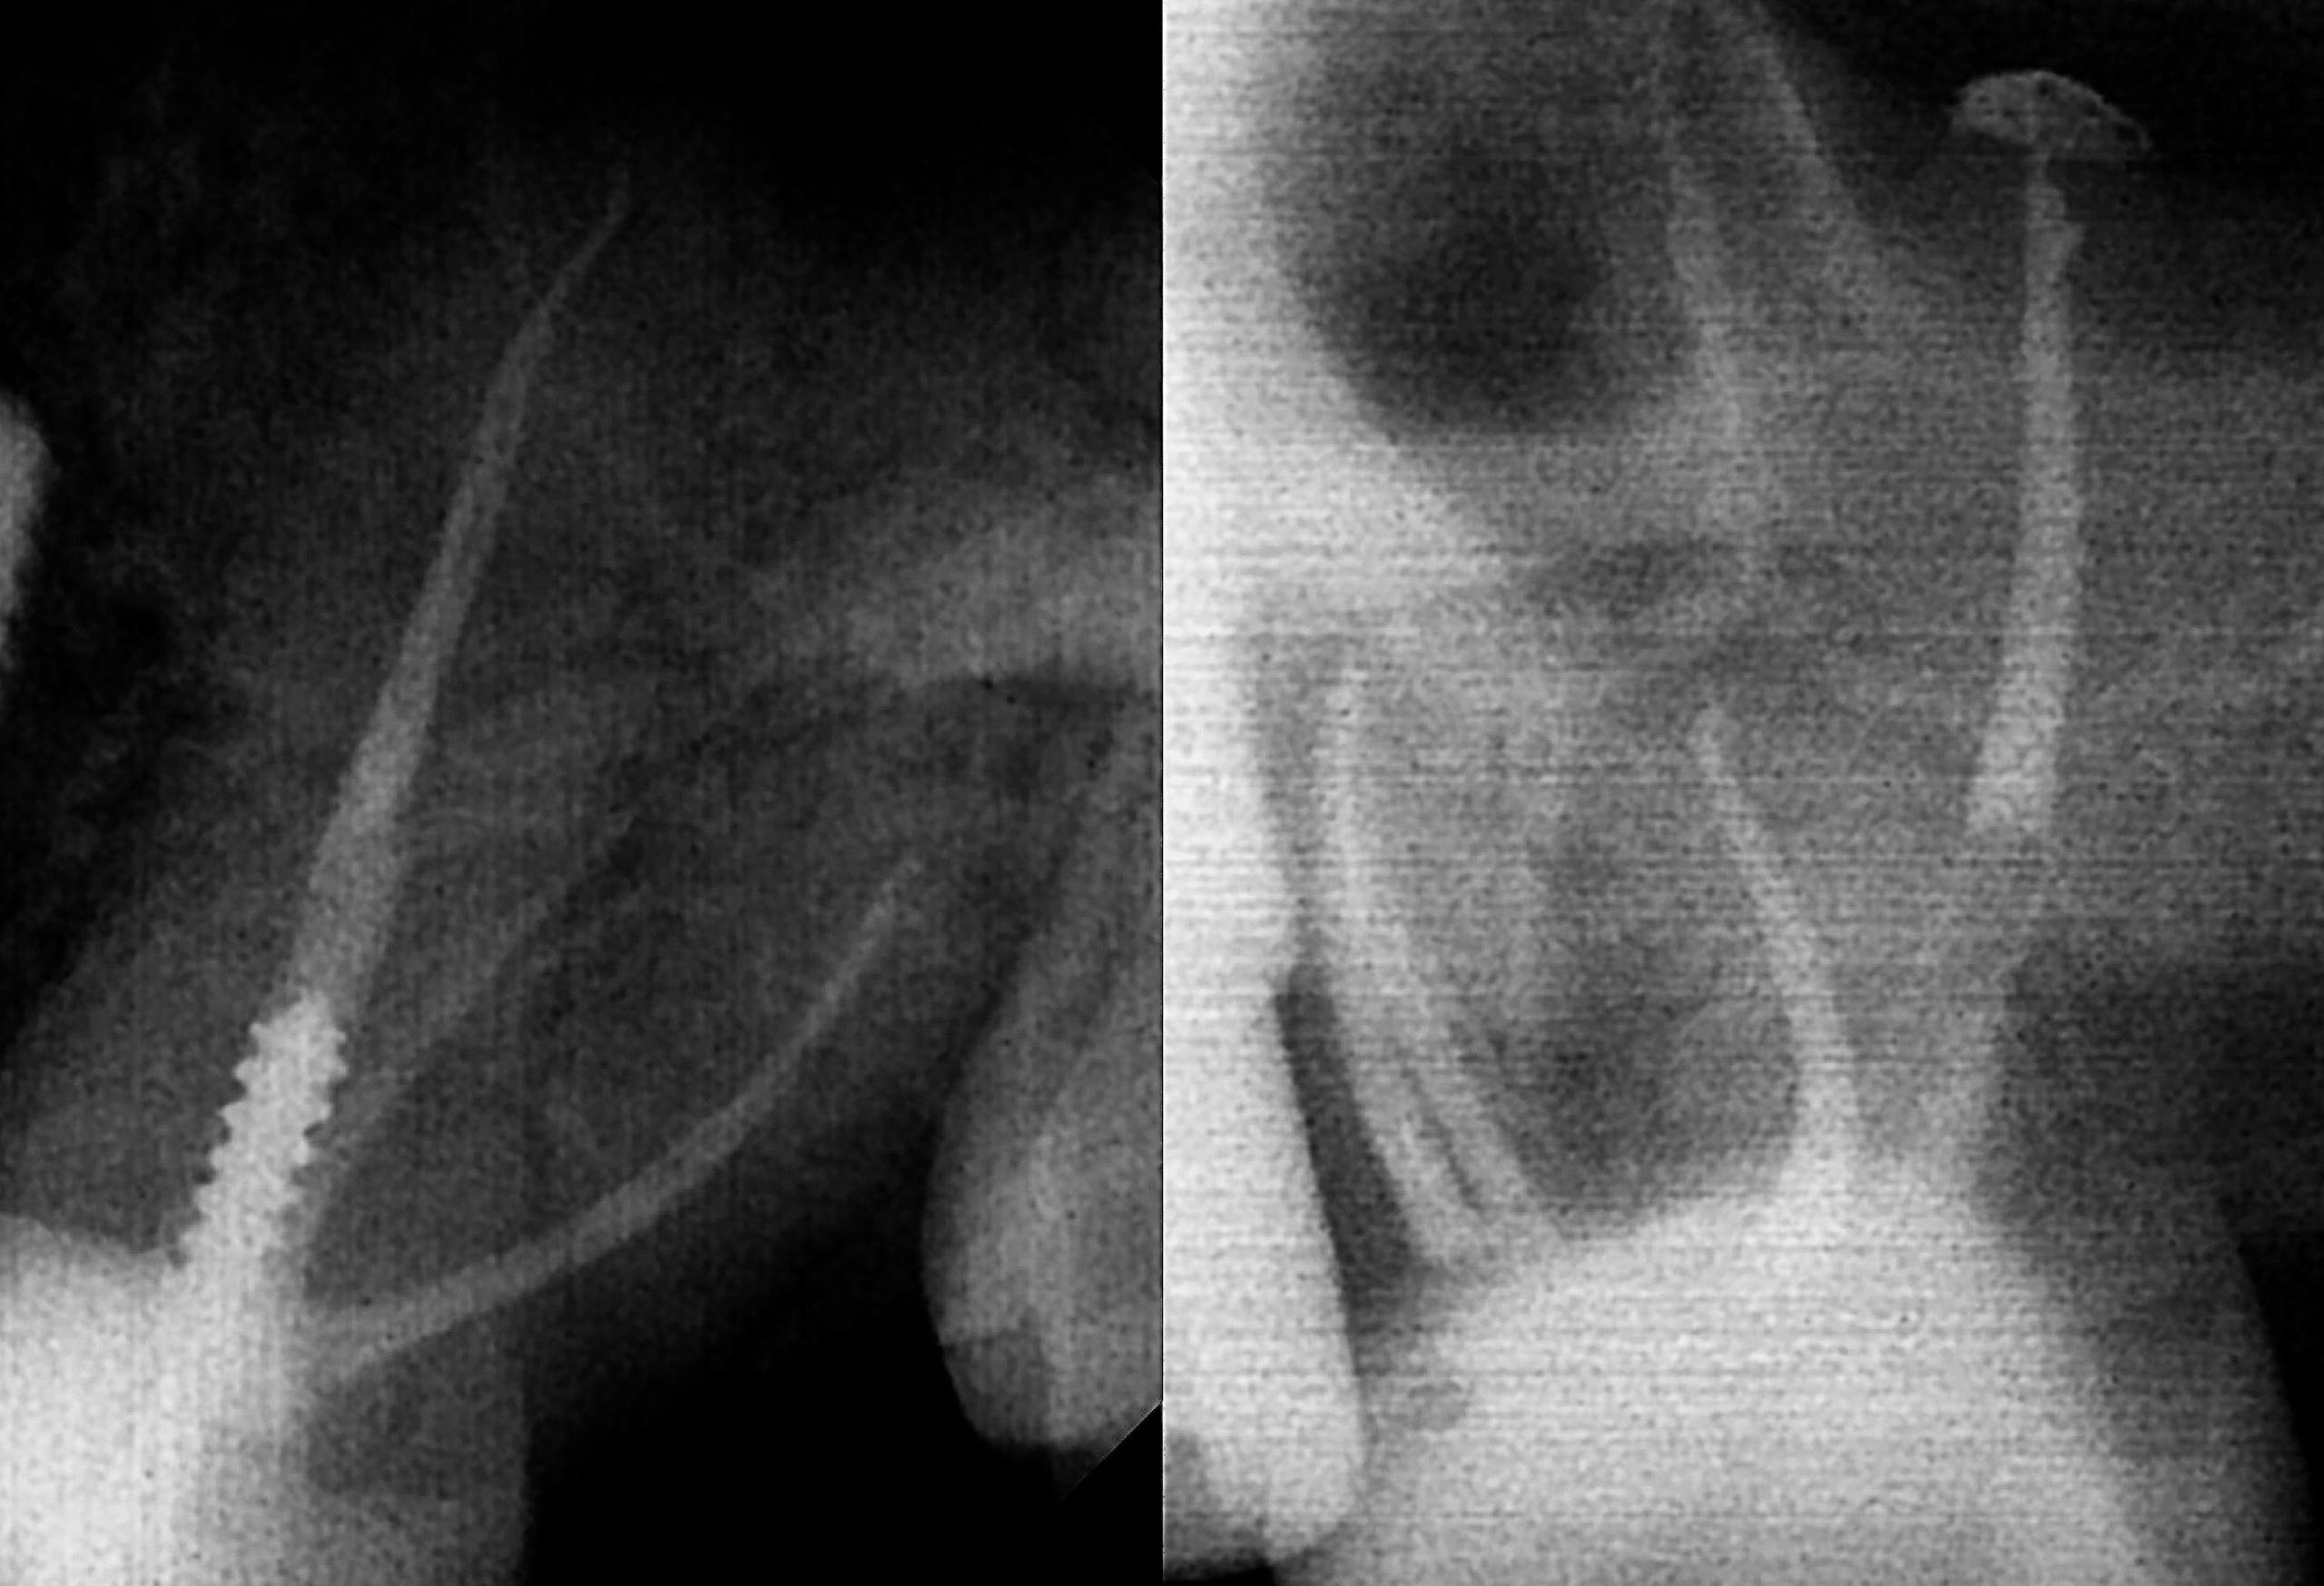

🦷 Рутинное перелечивание каналов.

1. Распломбировка как всегда Soco pro 25.06;

2. Mb1 Soco SC 04/30;

3. Mb2 04/25;

4. D 04/30;

5. P 04/40.

🔹Обтурация АН+ и гуттаперча гибридной методикой

Автор: Иван Шепелев